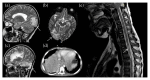

The immune system is a complex system able to recognize a wide variety of host agents, through different biological processes. For example, controlled changes in the redox state are able to start different pathways in immune cells and are involved in the killing of microbes. The generation and release of ROS in the form of an "oxidative burst" represent the pivotal mechanism by which phagocytic cells are able to destroy pathogens. On the other hand, impaired oxidative balance is also implicated in the pathogenesis of inflammatory complications, which may affect the function of many body systems. NADPH oxidase (NOX) plays a pivotal role in the production of ROS, and the defect of its different subunits leads to the development of chronic granulomatous disease (CGD). The defect of the different NOX subunits in CGD affects different organs. In this context, this review will be focused on the description of the effect of NOX2 deficiency in different body systems. Moreover, we will also focus our attention on the novel insight in the pathogenesis of immunodeficiency and inflammation-related manifestations and on the protective role of NOX2 deficiency against the development of atherosclerosis.